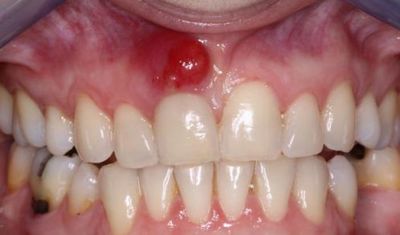

Фото 4. Гранулёма, возникшая из-за периодонтита. Представляет из себя припухлость на десне.